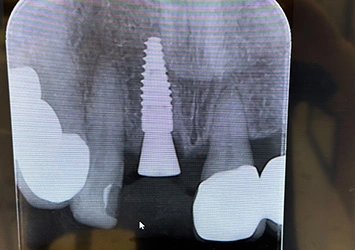

治療前

治療前写真 恵比寿南DENTAL 治療前写真 恵比寿南DENTAL

施術内容

【20代女性】

右下7番の歯根破折してしまい保存不可能となってしまった歯を抜歯し、インプラント埋入

治療期間

5ヶ月

リスク

術中の不可抗力によるトラブル(出血など)、術後注意事項を守らないことによる疼痛、感染、上部構造装着後口腔内清掃を怠ったことによるインプラント周囲組織の炎症

副作用

治療後の口腔内清掃、及びメインテナンスを怠ったことによるインプラント周囲粘膜炎またはインプラント周囲炎

費用

インプラント埋入:30万円

ジルコニアクラウン:12万円